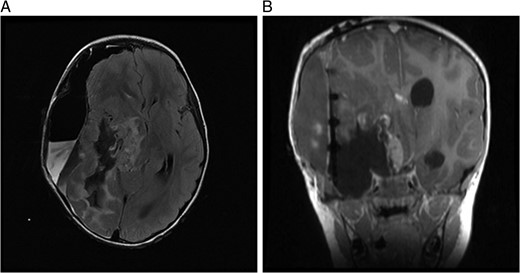

(A) MRI immediately following initial debulking of tumour showing a large subdural collection in a T2 FLAIR image and (B) coronal MRI post-op.

MRI 1 month post-op showed that the residual tumour in the basal ganglia, which extended inferiorly to the cerebellar pontine region had grown slightly larger. Also noted was a subdural fluid collection overlying the right cerebral hemisphere with extension into the interhemispheric fissure. Further debulking was carried out on the residual tumour. An MRI immediately post-op showed only 8mm of the tumour lying adjacent to the brainstem remained, which had previously measured 5.2 cm.